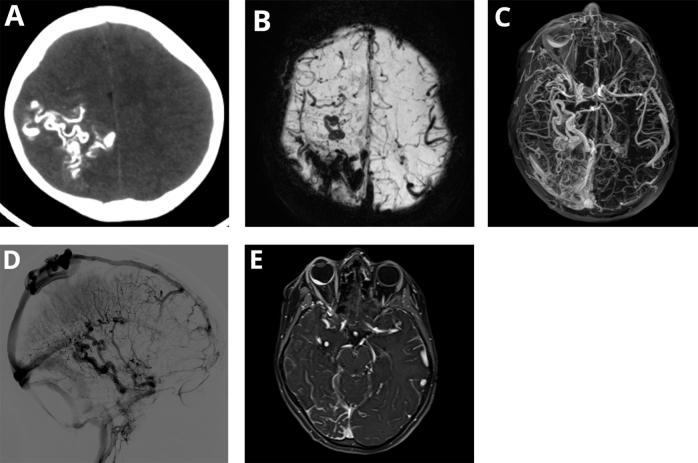

Case presentation: An 11-year-old boy, previously diagnosed with Sturge-Weber syndrome (SWS) Type I, presented to the emergency department with acute neurological symptoms that included vomiting, headaches, left-sided hemiparesis, and right-sided deviation of the labial commissure.

Clinical discussion: Sturge-Weber syndrome (SWS) is a rare neurocutaneous disorder characterized by facial port-wine stains, leptomeningeal angiomas, and ocular involvement. Our case presented with preserved cognition despite extensive temporal lobe angiomatosis, contrasting the typical presentation of seizures and developmental delay. The patient then experienced stroke-like episodes from fragile leptomeningeal vasculature. With anticonvulsants and low-dose aspirin therapy, the patient achieved full neurological recovery within the first 3 months and maintained stability during 2 years of follow-up.

Conclusion: This case underscores the diverse clinical spectrum of Sturge-Weber syndrome and emphasizes the crucial role of imaging in achieving an accurate diagnosis. Early identification and treatment are essential to prevent further complications and optimize patient outcomes.